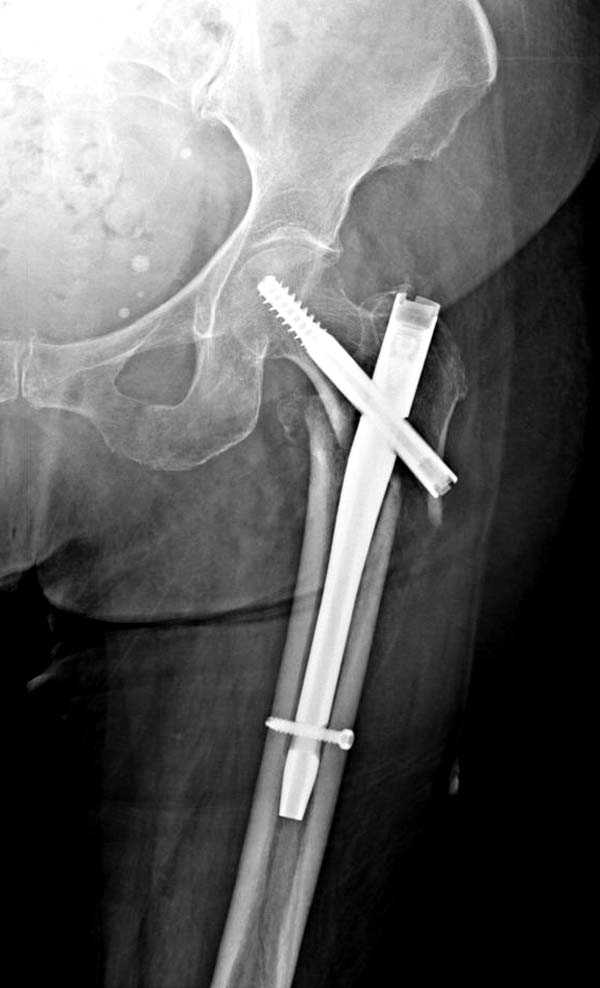

Здесь представлен случай, где в послеоперационном периоде обнаружена техническая ошибка, Gamma 3 установлен с нарушением методики. Больная в 91 лет, прооперирована через день после поступления и выписана через 48 часов.<br>

При первом послеоперационном поликлиническом осмотре больная предъявила жалобы на боли в бедре. В серийных снимках обнаружен продольный перелом верхнего отдела бедра.<br>

Считаем, что техническая ошибка произошла во время установки гвоздя, когда рассверливанию канала не уделили должного внимания. Канал остался узковат, и гвоздь был забит с силой.

Полная нагрузка конечности приостановлена на две недели, и боли в конечности изчезли. Больная начала нагрузку и перелом срастается.